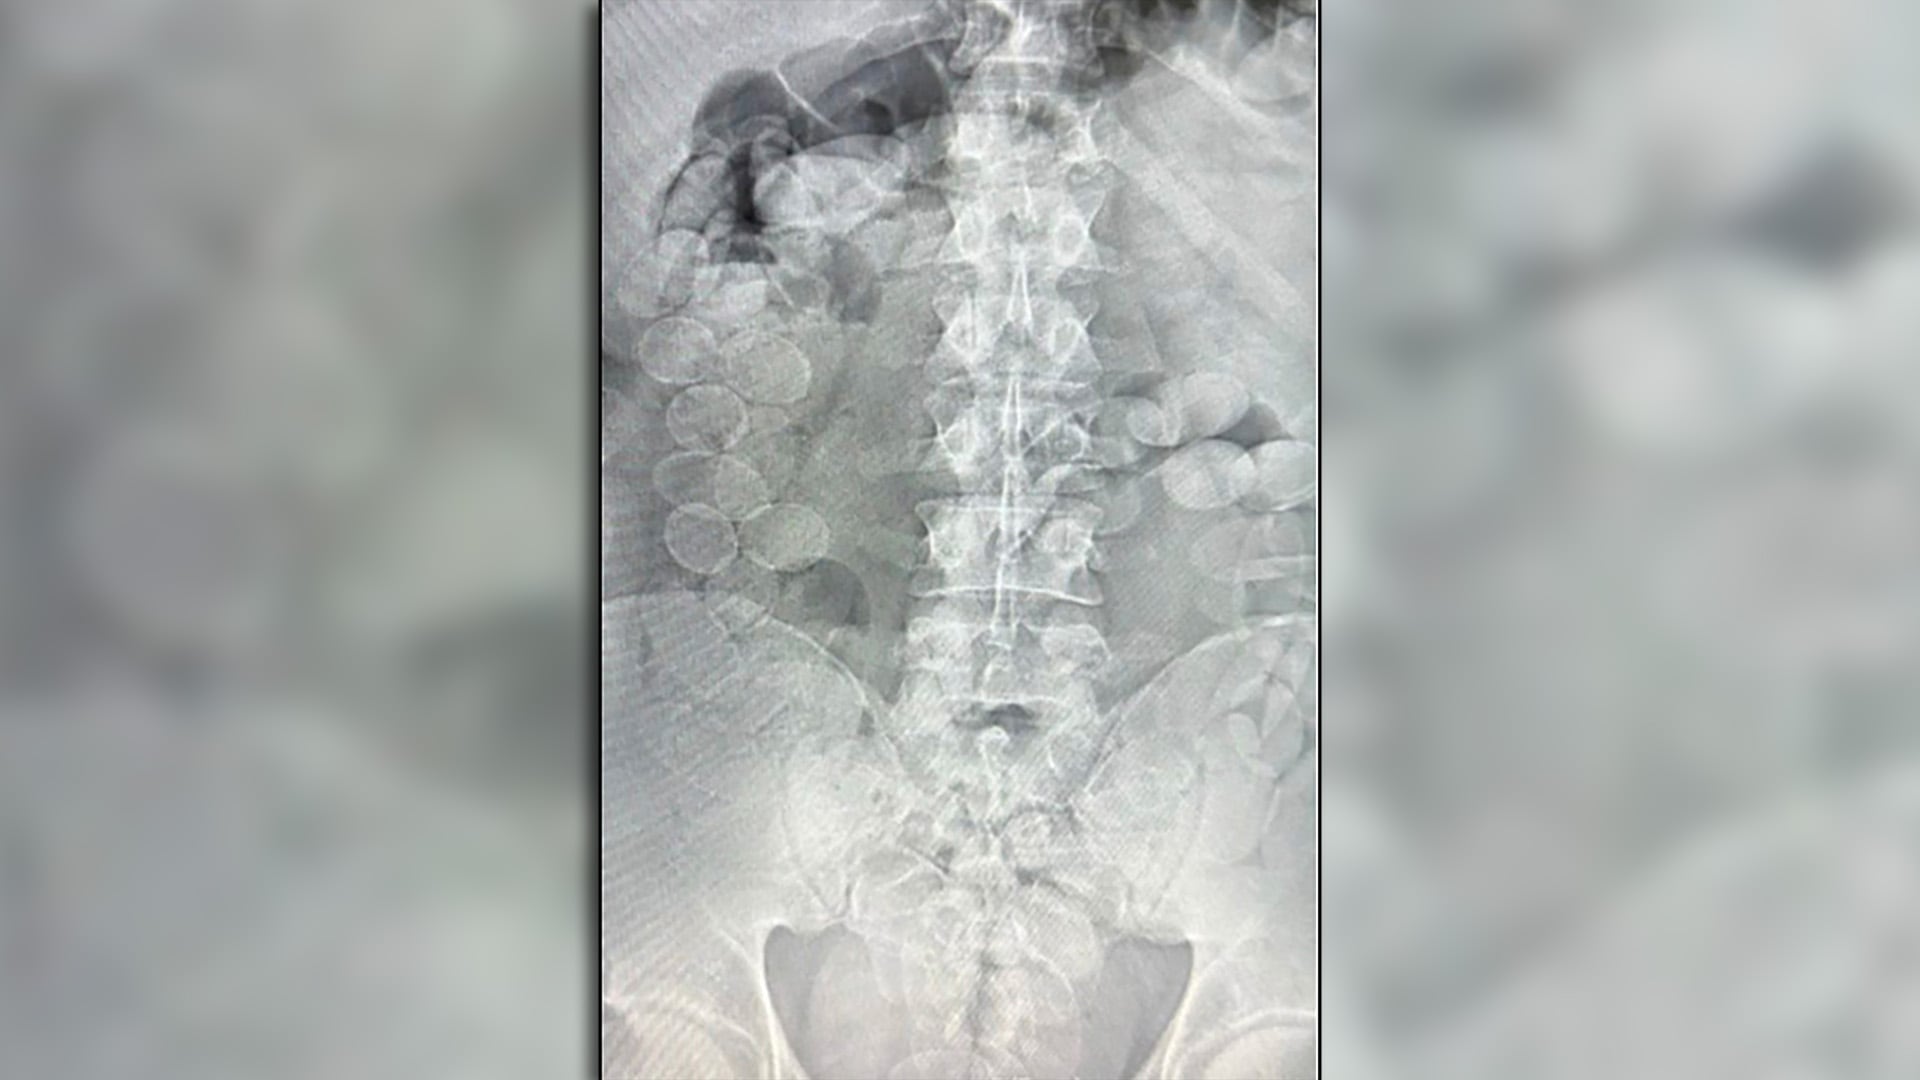

El impacto le provocó a Farfán lesiones de gravedad, entre ellas la fractura de una pierna y otras complicaciones que llevaron al equipo médico a amputarle una extremidad. Pese a los esfuerzos del cuerpo clínico y la intervención quirúrgica, el joven sufrió un paro cardiorrespiratorio y falleció en la tarde del lunes.